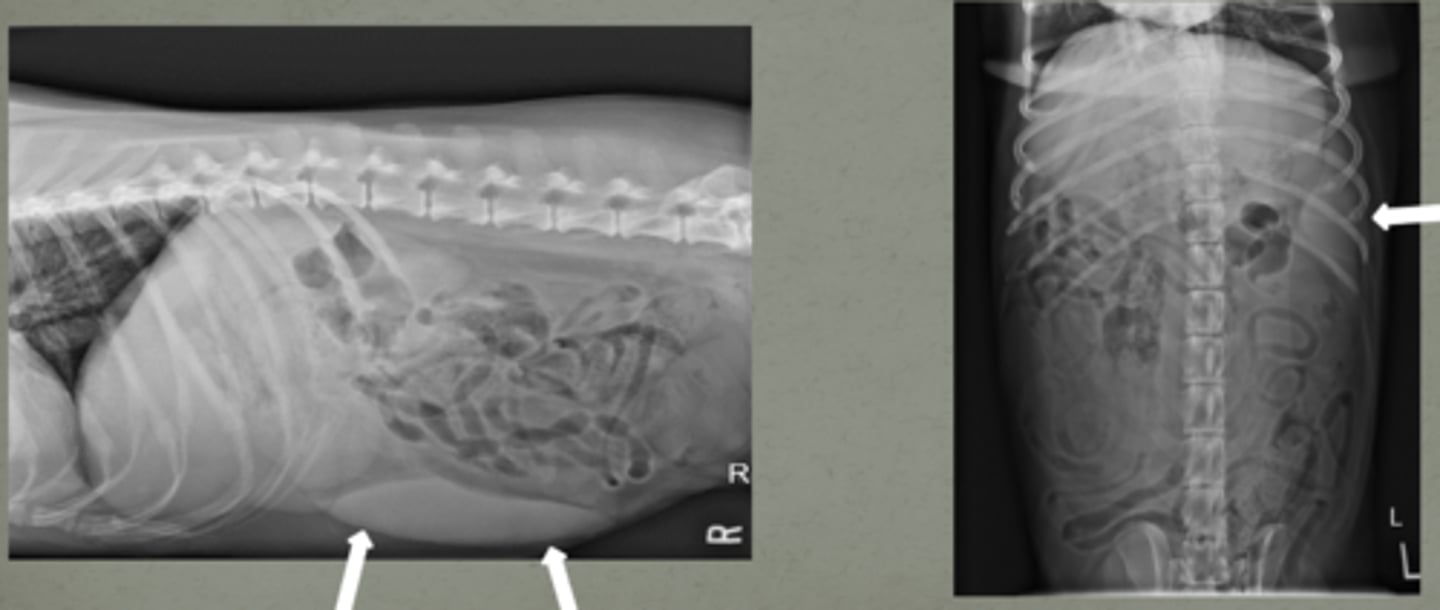

shadowing underneath the mass

if there is a hyperechoic mass in the spleen, what artifact will occur due to it?

shadowing due to the splenic mass

what are the arrows indicating? (there is a mass in this spleen)